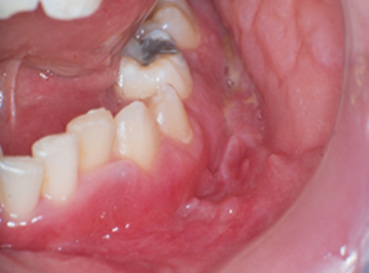

Another lesion that has received attention in the literature is the cobblestone appearance of the mucosa occasionally seen in patients with CD. Linear, indented ulcerations separated by normal mucosa has the appearance of cobblestones. This is not an uncommon finding in persons with CD, with a reported prevalence of 6% in children and 20% in adults5Lauritano D, Boccalari E, Di Stasio D, Della Vella F, Carinci F, Lucchese A, et al. Prevalence of oral lesions and correlation with intestinal symptoms of inflammatory bowel disease: A systematic review. Diagnostics (Basel). 2019;9(3).. Persons with CD can also demonstrate swelling of the oral mucosa, most often on the buccal surface and in the retromolar area, as well as extra-orally, affecting the face and lips. If the lips are involved, painful fissures can develop. If occurring extra-orally, these swellings can present an esthetic concern for patients. Histologic examination of these swellings suggests a granulomatous inflammation6Mejia LM. Oral manifestations of gastrointestinal disorders. Atlas Oral Maxillofac Surg Clin North Am. 2017;25(2):93-104..